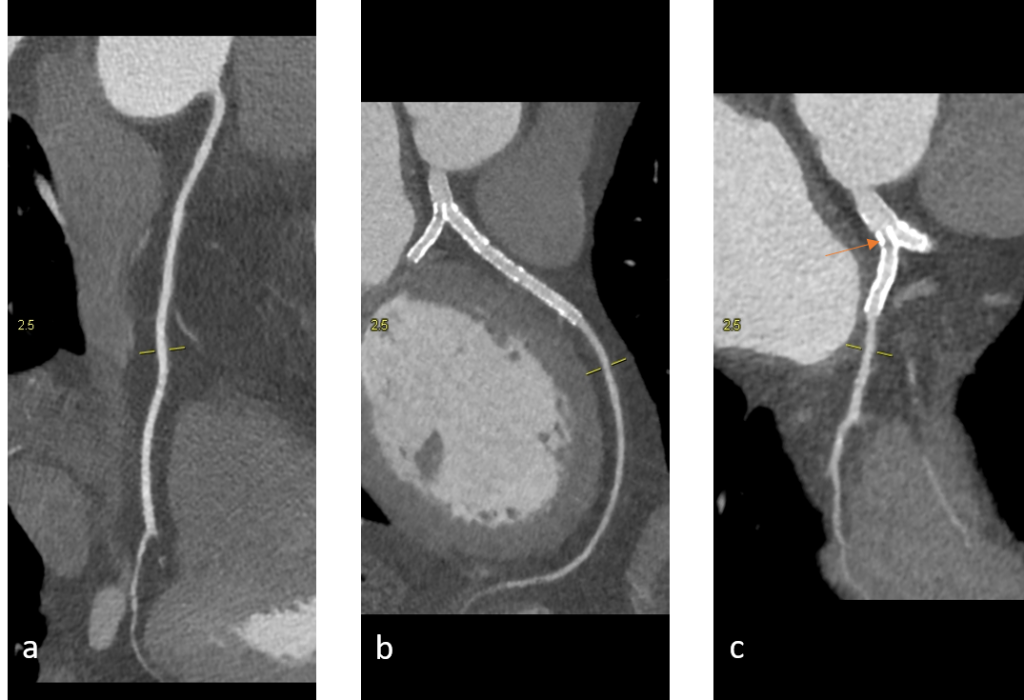

Stenturile situate proximal la nivelul arterelor coronare au lumen suficient de mare ca să poate fi vizualizat prin CT, însă cu cat lumenul e mai mic şi / sau cantitatea de metal din peretele stentului este mai mare, lumenul stentului e mai greu de vizualizat. Examinarea CT NU poate vizualiza sensul de curgere al sângelui, de aceea faptul că după stent se pune în evidenţă densitate intraluminală egală cu cea din vasele de vecinătate, nu înseamnă ca stentul este permeabil; contrastul poate că a ajuns aici prin colaterale ca flux retrograd.

Stenturile coronariene proximale sunt în general corect evaluate prin examinare angioCT cardiacă cu sincronizare ECG pe aparate cu cel putin 64 de detectori. Prin examinare CT nu se poate vizualiza sensul de curgere a sângelui.